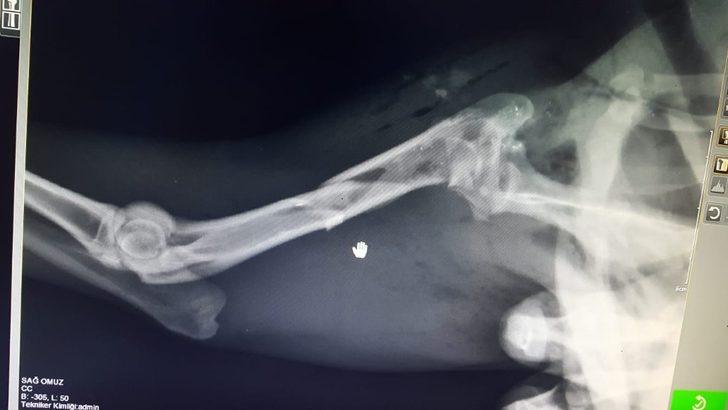

Balıkesir Bigadiç ilçesi Adalı kırsal mahallesinde avcılar tarafından 5 farklı yerinden vurularak yaralanan Karaca’yı fark eden vatandaşlar Balıkesir Doğa Koruma ve Milli Marklar Müdürlüğüne haber verdi. Büyükşehir Belediyesi Çevre Koruma Kontrol Daire Başkanlığı ekiplerince Ovaköy Sokak Hayvanları Geçici Bakımevi’ne getirilen Karaca, yapılan acil müdahalenin ardından tedaviye alındı. Sağlığına kavuşan Karaca Balıkesir Doğa Koruma ve Milli Marklar Müdürlüğü’ne teslim edildi. Yaralı Karaca’ya ilk müdahalede bulunan Veteriner Hekim Serhat Meşe yaptığı açıklamada “Ovaköy Geçici Bakım Evi’nde nöbetçi veteriner hekimlerimizce yapılan muayenenin ardından kan kaybı olan ve 5 yerinden ateşli silah yarası olduğu tespit edilen Karaca operasyona alındı. Karın bölgesi ve sırt bölgesindeki yaralar kapatıldı. Detaylı röntgen görüntüsü için İvrindi Sokak Hayvanları Geçici Bakım Evi’ne sevk edildi. Çekilen radyografi görüntüsü sonucu sağ ön kol kemiğinde kırık tespit edildi. 2 günlük tedavinin ardından yaşam fonksiyonlarını kazanan Karaca’nın kırık kemik uçlarının ameliyatı için Milli Parklar yetkililerine teslim edildi. Milli Parklar yetkilileri ön kol ameliyatının gerçekleştirilmesi üzerine karacayı teslim alarak Uludağ Üniversitesi veteriner fakültesine sevki gerçekleştirildi" dedi.